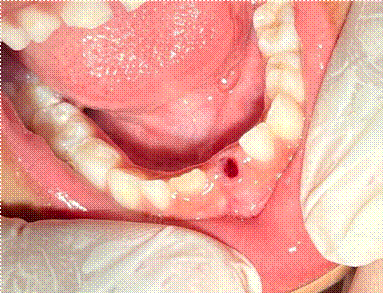

Figura 1 – Foto inicial

Fonte – Elaborado pelo autor

A motivação atual pela busca por assistência odontológica se dá pela a mobilidade acentuada do elemento dentário 71, incisivo central inferior esquerdo decíduo, suspeitando-se de rizólise fisiológica e início do período de esfoliação dentária. A paciente não permite que os pais tendem a extração domiciliar, devido à sensibilidade tátil e resistência à manipulação, o que reforçou a necessidade de intervenção profissional.

A exodontia do incisivo central deciduo inferior esquerdo, elemento dentário 71 então foi realizada. Utilizado o abridor de boca tipo abritec, utilizado para manter a estabilidade da abertura bucal. Os instrumentais cirúrgicos utilizados incluíram o descolador de Molt, empregado para descolar delicadamente a gengiva marginal e a papila adjacente ao elemento dentário. Em seguida, utilizou-se o fórceps pediátrico nº01 para incisivos decíduos, aplicando-se movimentos controlados de luxação e tração, culminando na extração bem-sucedida do dente em um tempo cirúrgico mínimo.

O procedimento transcorreu sem intercorrências e com sangramento mínimo, devido à natureza simples da exodontia do elemento decíduo e à integridade dos tecidos circundantes, não houve a necessidade de sutura, a hemostasia foi obtida apenas com o auxílio de compressão com gaze estéril.